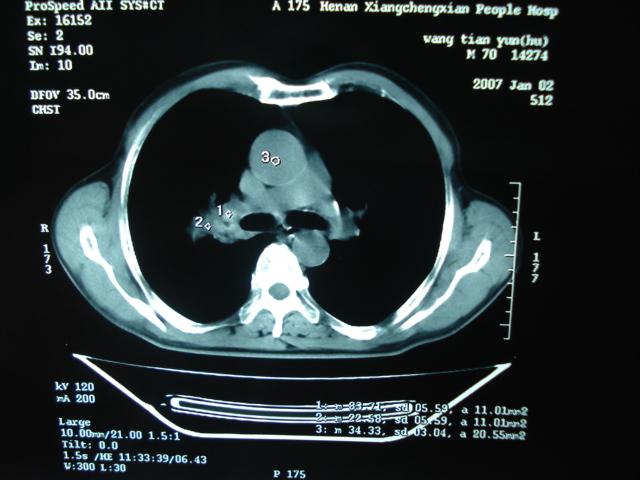

以下是引用狙击手在2007-4-18 20:17:00的发言:[br]原:2007/1/22号ct片:右肺上叶可见片状、云雾状高密度影,右肺上叶后段可见三角形高密度影,尖端指向肺门,右肺上叶后段支气管壁不规则增厚,管腔不规则增厚,纵隔未见肿大淋巴结.[br] 今ct:右肺上叶片状影增大,右肺上叶后段不张及右肺上叶后段支气管壁不规则增厚未见变化,右肺下叶背段支气管壁不规则增厚.[br] 如果考虑肺结核,但从临床证据看竟然没有一项支持肺结核,不知患者是否已经过正规抗结核治疗。没有的话,3个月了前后片看起来变化不大,似乎有不太符合肿瘤征象,不知患者是否抗炎治疗过,下叶支气管增粗还是要高度警惕,同意楼主意见,将常规病理,生化检查再做一遍。[br]

以下是引用狙击手在2007-4-18 20:17:00的发言:[br]原:2007/1/22号ct片:右肺上叶可见片状、云雾状高密度影,右肺上叶后段可见三角形高密度影,尖端指向肺门,右肺上叶后段支气管壁不规则增厚,管腔不规则增厚,纵隔未见肿大淋巴结.[br] 今ct:右肺上叶片状影增大,右肺上叶后段不张及右肺上叶后段支气管壁不规则增厚未见变化,右肺下叶背段支气管壁不规则增厚.[br] 如果考虑肺结核,但从临床证据看竟然没有一项支持肺结核,不知患者是否已经过正规抗结核治疗。没有的话,3个月了前后片看起来变化不大,似乎有不太符合肿瘤征象,不知患者是否抗炎治疗过,下叶支气管增粗还是要高度警惕,同意楼主意见,将常规病理,生化检查在做一遍。[br]